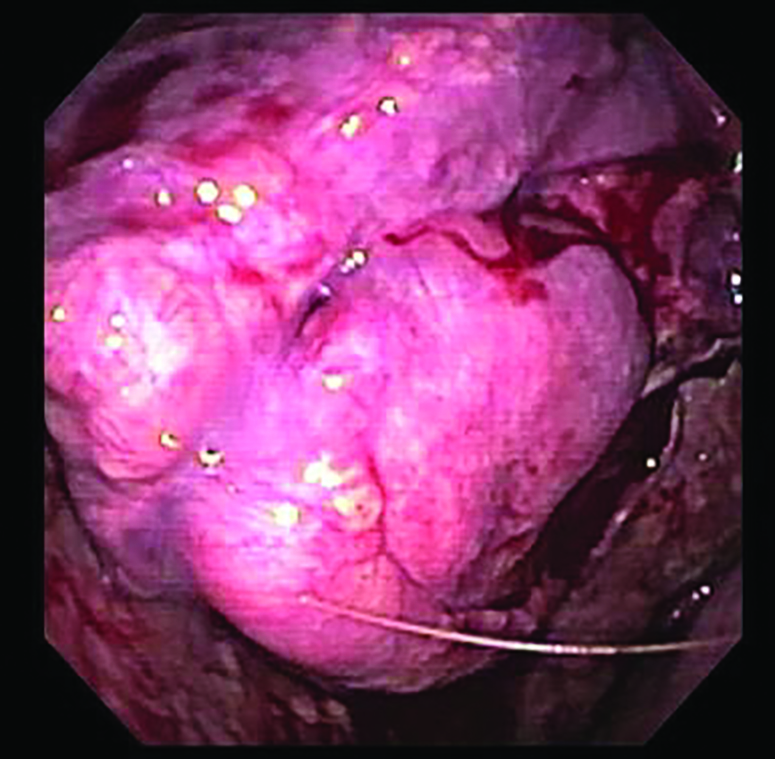

Figure 2

Figure 2. Pleuroscopy Image 1 – Endoscopic view of the parietal pleura showing multiple granular tumor-like lesions with a friable surface. These were noted during diagnostic pleuroscopy under general anesthesia with double-lumen intubation.

Figure 3

Figure 3. Pleuroscopy Image 2 – Close-up of pleural lesions demonstrating abnormal vascularity and nodularity consistent with metastatic involvement.